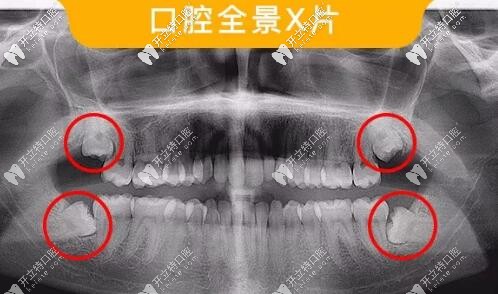

多生牙全景片

多生牙一般分萌出和不萌出埋伏阻生兩種,有些牙齒還倒長。

多生牙在任何牙位都可能發(fā)生多生牙,但常見的是上頜“正中多生牙”,其后,依次排為上頜第四磨牙等。